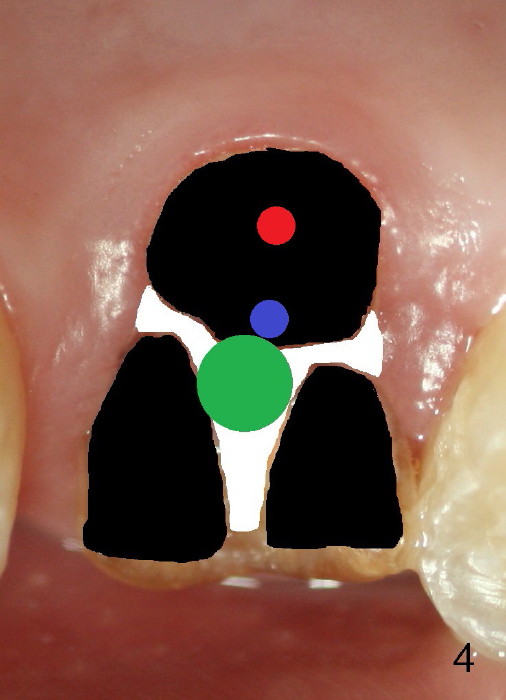

By the time a 2.6 mm bone expander is used, the septum starts to break off (Fig.4 green). The osteotomy site has to be changed: first to the palatal slope of the palatal socket (red) with the coronal end of the drill leaning buccally. Suddenly a better idea occurs: new osteotomy remains in the palatal socket, but as buccally as possible (blue) and finishes with rounded tapered osteotomes 2-4 mm at ~17 mm deep. The coronal end of the osteotomes is controlled to be positioned in the center of the socket (Fig.5 blue).